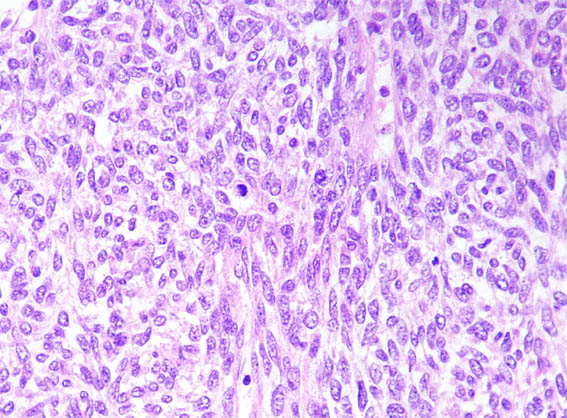

The patient is a 2-month-old boy in whom his mother palpates abdominal mass. Image studies demonstrate mass that compromises more than 50% of the left kidney.

Nephrectomy is done. Look at the pictures.

Figure 2. H&E, X100.

Figure 3. H&E, X100.

Figure 4. H&E, X100.

Figure 5. H&E, X200.

Figure 6. H&E, X200.

Figure 7. H&E, X400.

Figure 8. H&E, X400.

Figure 9. H&E, X400.